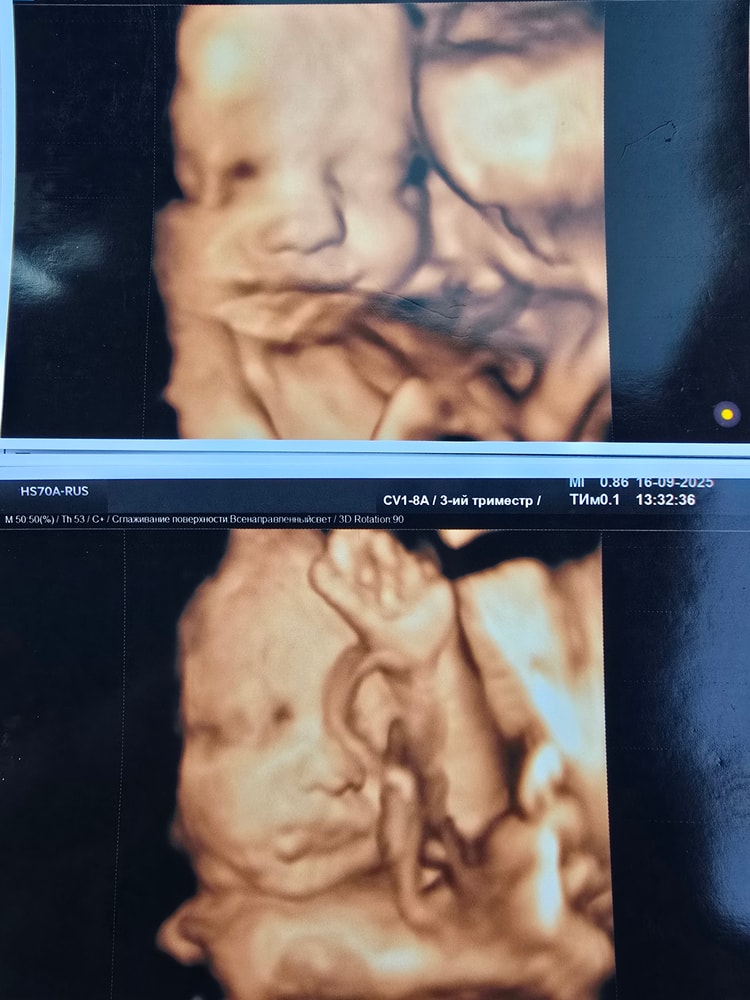

Анализы, скринингиСходила на скрининг на сроке беременности 30+5 недель. Малышка лежит попой вниз, ноги закинула к голове. Врач предположил, что она может перевернуться.

Вес ребёнка — 1588 граммов. По результатам УЗИ всё в норме.

Моя лапушка 🥹❤️